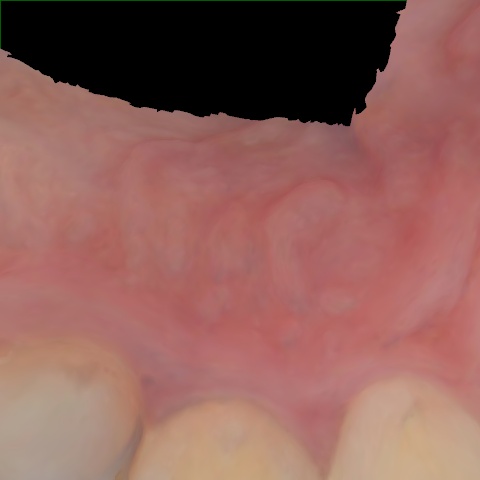

Image 1070 / 1535

NHD39990

Annotated as "Good"

Original Image Rendering Image